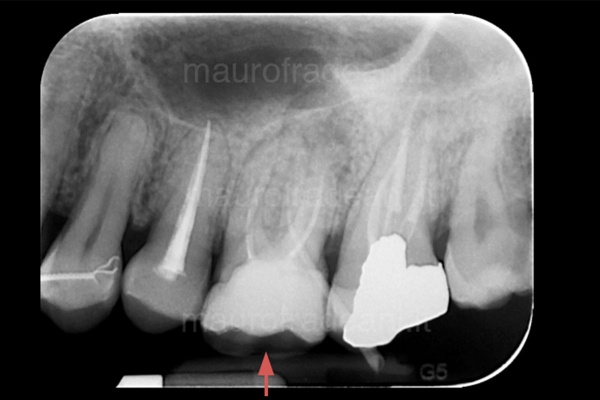

3/7: The pre-treatment X-ray shows a widespread problem of bone loss and the inadequacy of the previous prosthetic restorations.